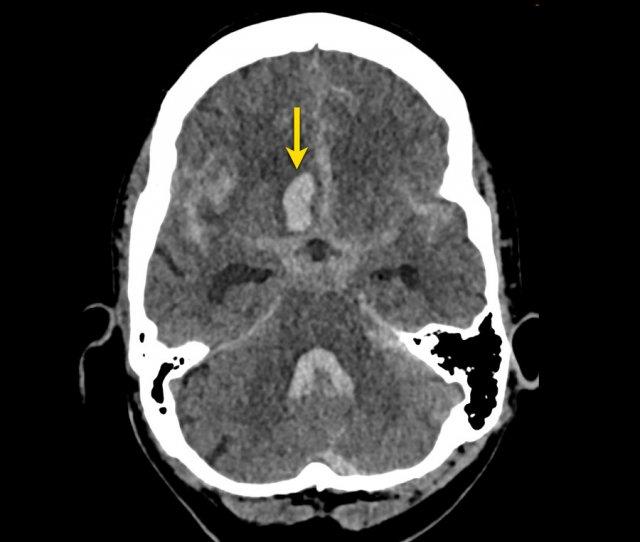

Đây là một ví dụ về xuất huyết dưới nhện trên NECT.

Lưu ý vị trí máu chủ yếu xung quanh thân não và trong não thất III và IV.

Thông thường, vị trí của máu dưới nhện giúp định hướng xác định vị trí của túi phình động mạch.

Bước tiếp theo là thực hiện chụp CT mạch máu (CTA) để tìm kiếm túi phình động mạch là nguyên nhân gây SAH.

Bệnh nhân này có túi phình tại nguyên ủy của động mạch tiểu não sau dưới trái (PICA).

Cũng cần lưu ý tình trạng não úng thủy.

Bệnh nhân này được thực hiện chụp mạch số hóa xóa nền (DSA) và sau đó được nút coil.

DSA cho thấy một túi phình hình túi của PICA trái, đường kính tối đa 6 mm với cổ ngắn và hẹp.

Phình động mạch hình túi là loại phình động mạch phổ biến nhất. Chúng có hình tròn hoặc thùy và xuất hiện tại các vị trí phân nhánh của đa giác Willis.